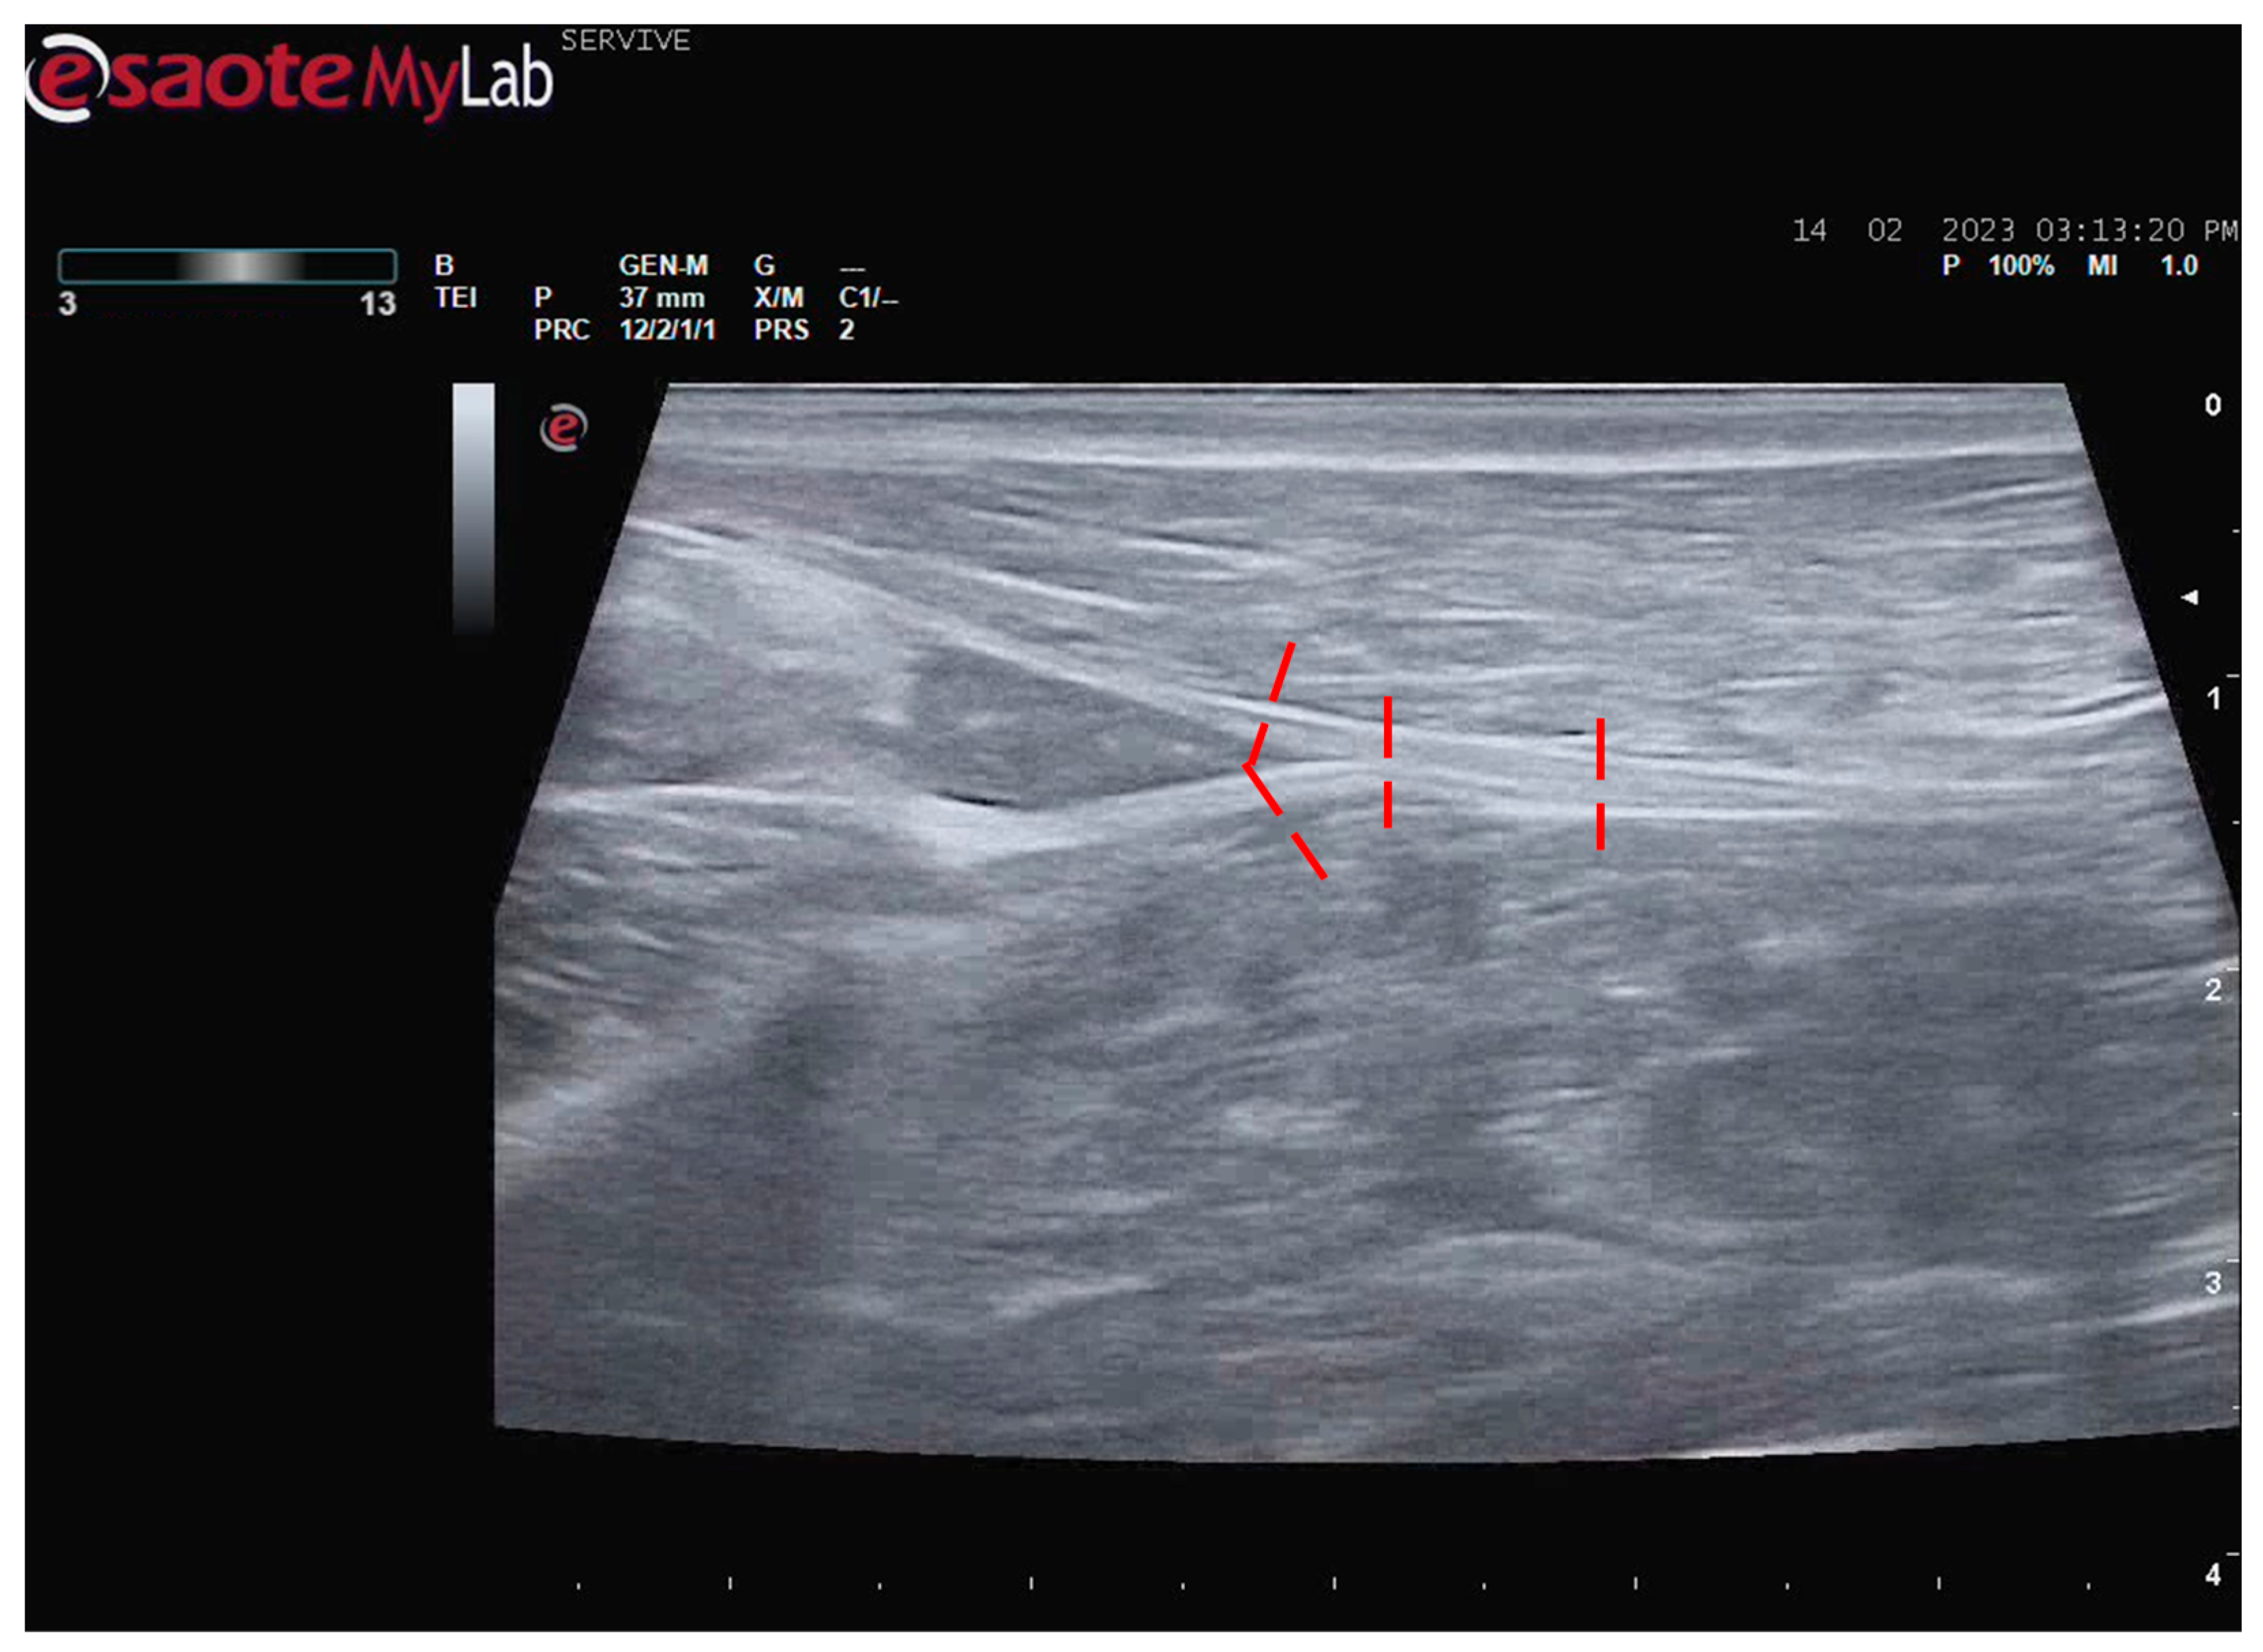

Figure 6.

Schematic representation of the measurement sites for the diameter of the sciatic, common peroneal, and tibial nerves. The measurement sites are identified by the red dashed lines.

The diameters of the sciatic nerve were measured in the middle of its course along the thigh and immediately before its division. The diameters of the common peroneal and tibial nerves were determined immediately after its diversion (Figure 6). The values obtained while measuring the diameters of the nerves of the 10 evaluated animals can be consulted in Table 1. The diameter of the sciatic nerve does not vary greatly between its course in the middle of the thigh and immediately before its branching site. Confirming the ultrasound observation, the diameter of the tibial nerve is systematically higher than that of the corresponding common peroneal nerve, distally to their branching site.